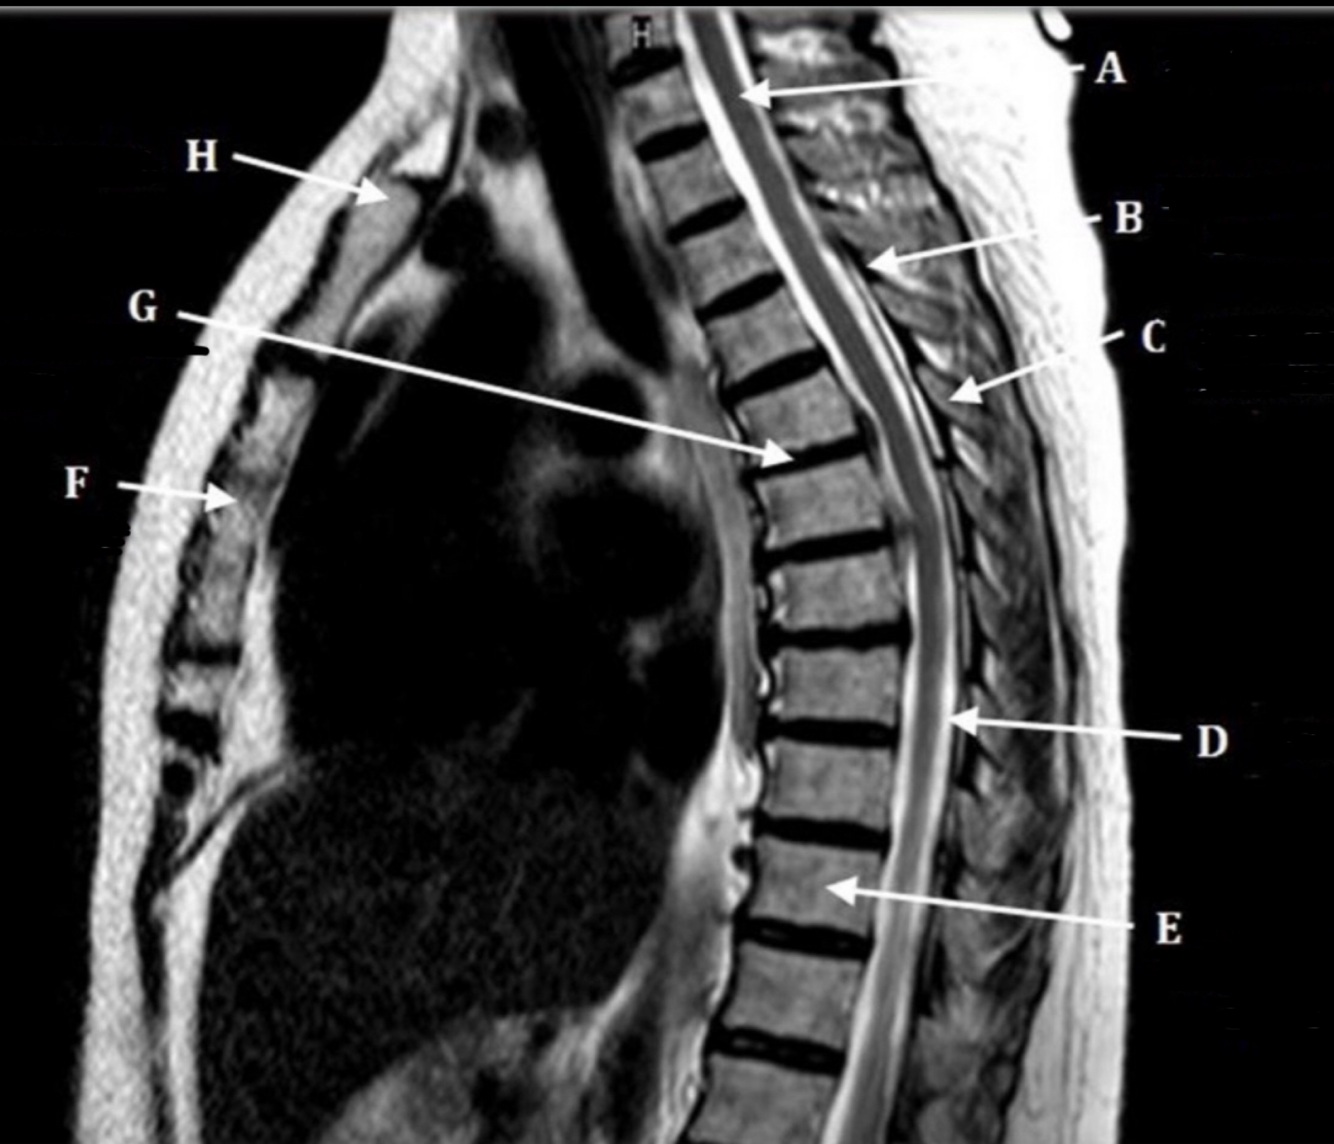

What is letter A?

SPINAL CORD

20

What is letter B?

LIGAMENTUM FLAVUM

21

What is letter C?

SPINOUS PROCESS

22

What is letter D?

CSF

23

What is letter E?

VERTEBRAL BODY

24

What is letter F?

STERNUM

25

What is letter H?

SUPRASTERNAL NOTCH